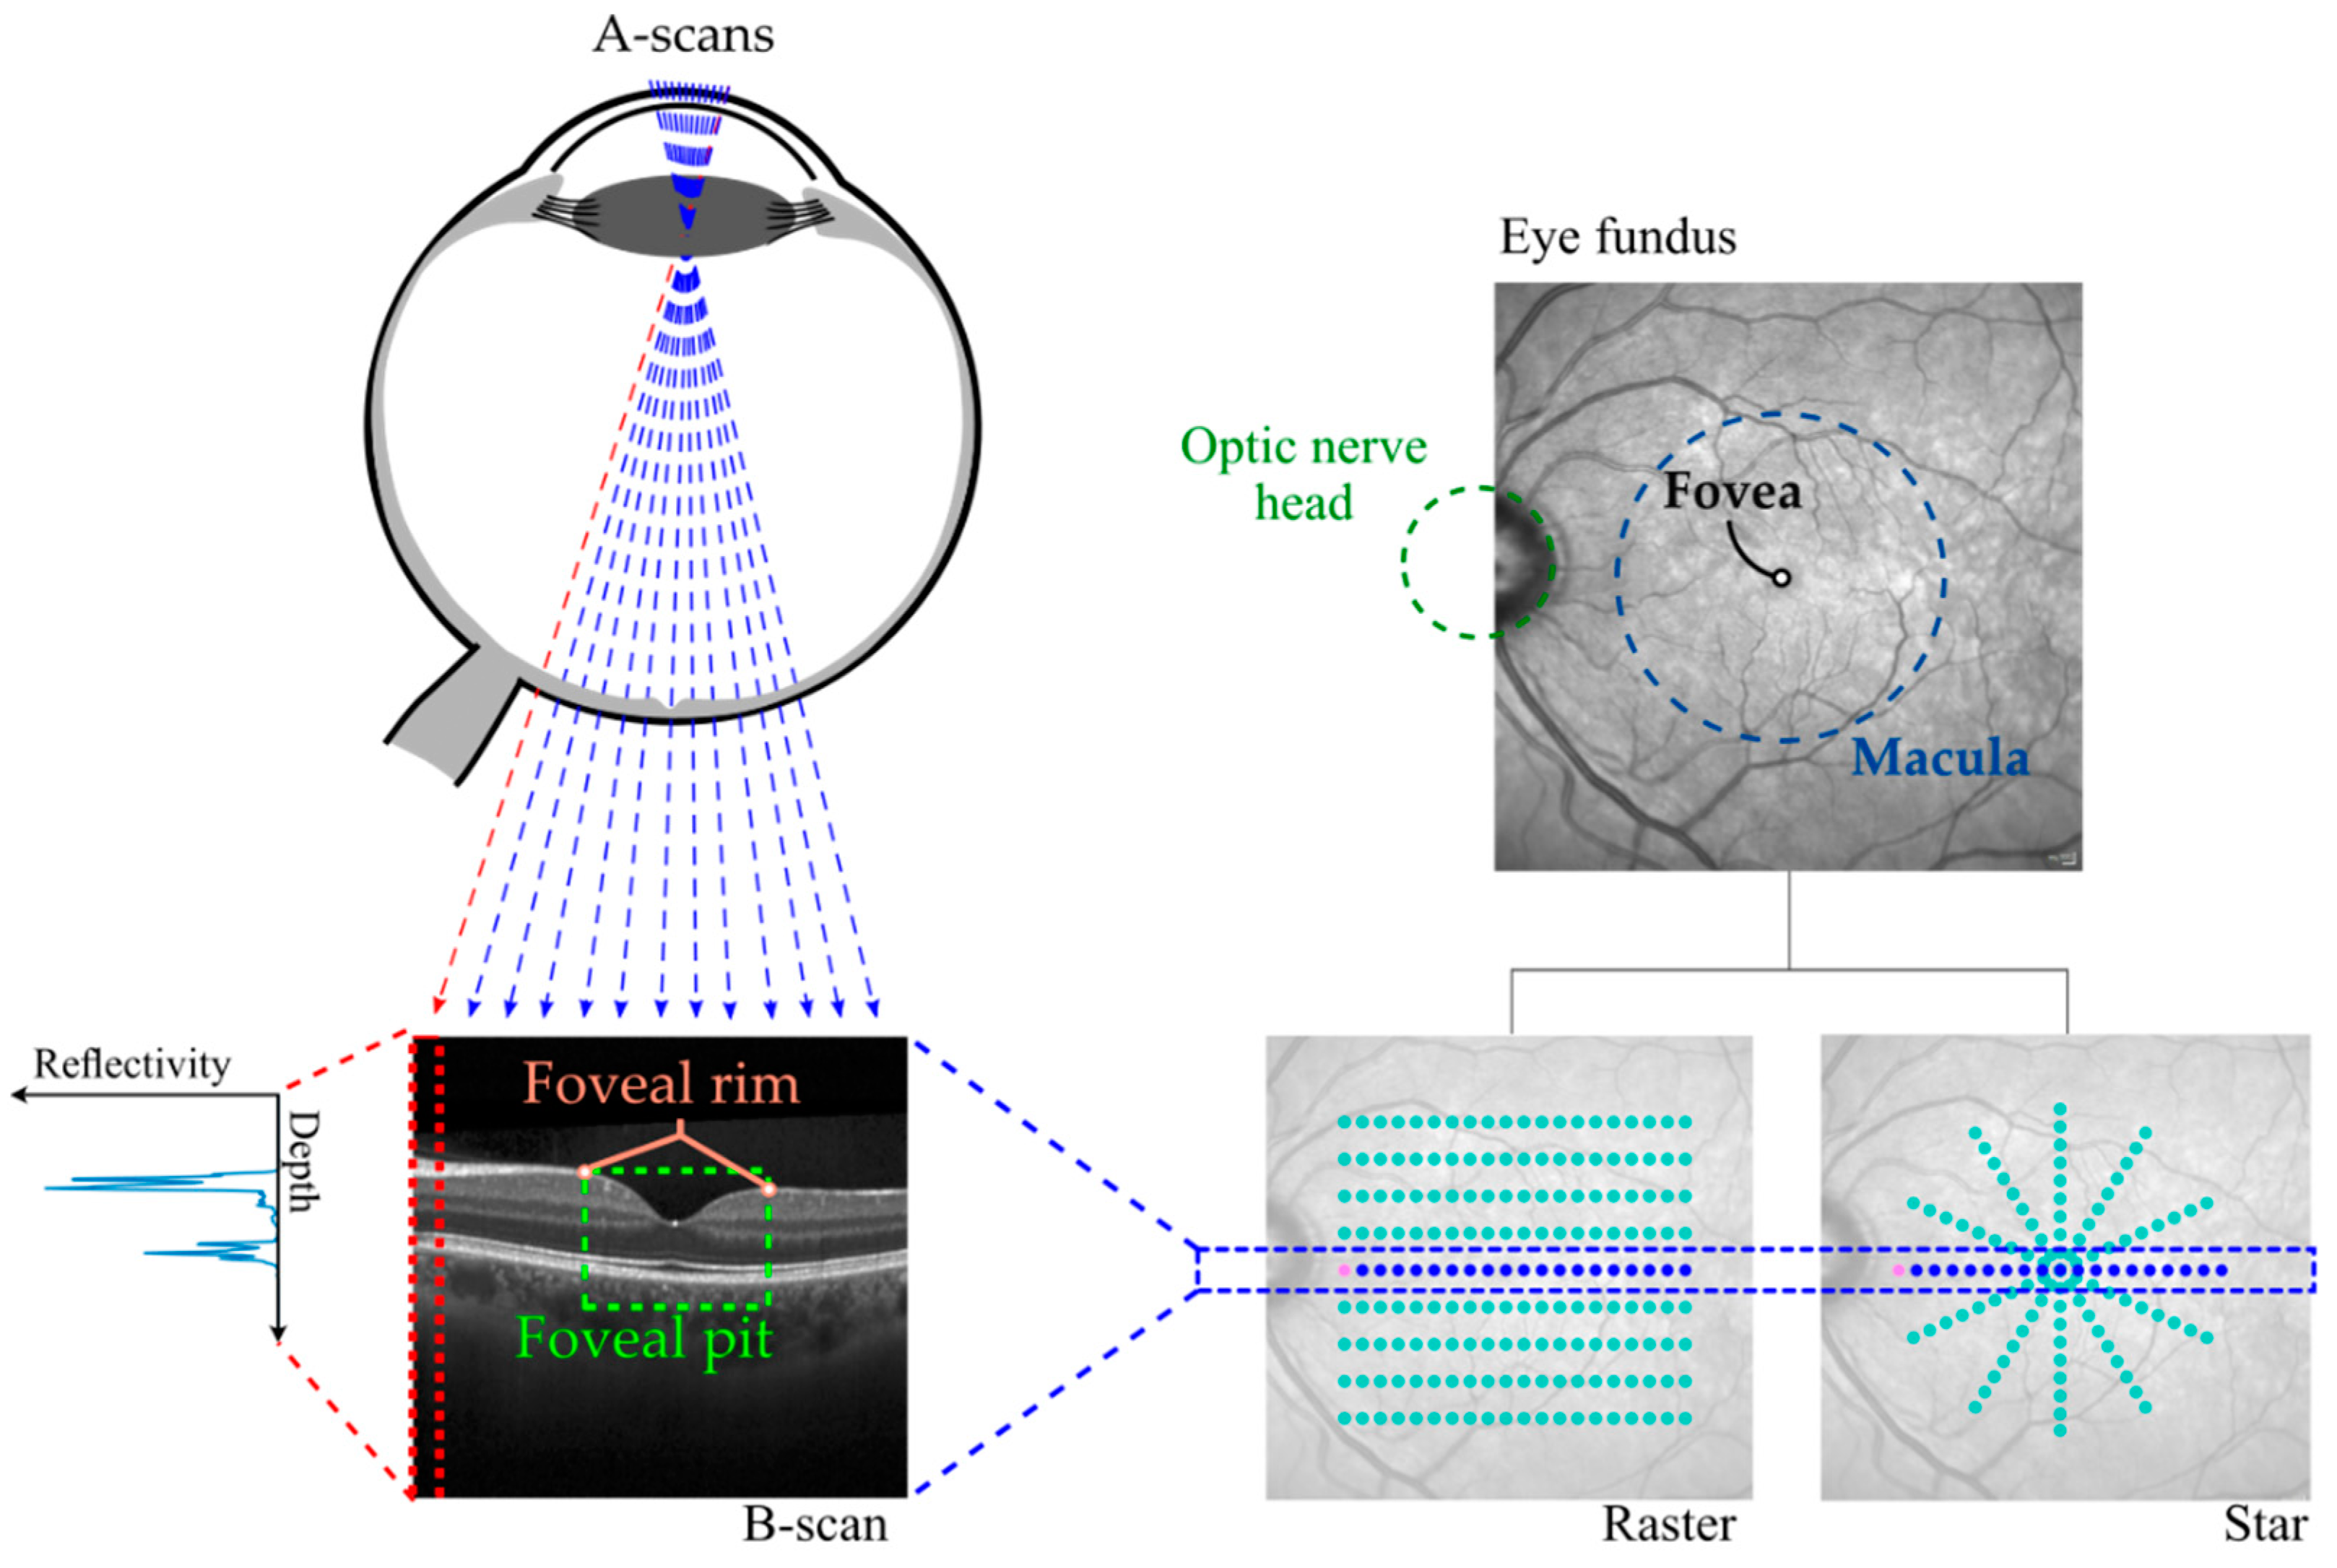

2.2. Image Acquisition

2.3. Image Processing Pipeline

- Regular grid of 3 × 3 mm2 and a spacing of 0.02 mm. This was used for foveal center location method comparison (see Section 2.4.1).

- Radial pattern with 2 mm radius, 24 angular directions and a spacing of 0.02 mm. This was used for morphology analysis and mathematical model comparison (see Section 2.4.2). This was calculated after using only the smooth + min method to locate the foveal center, as it was the method that provided the best alignment.